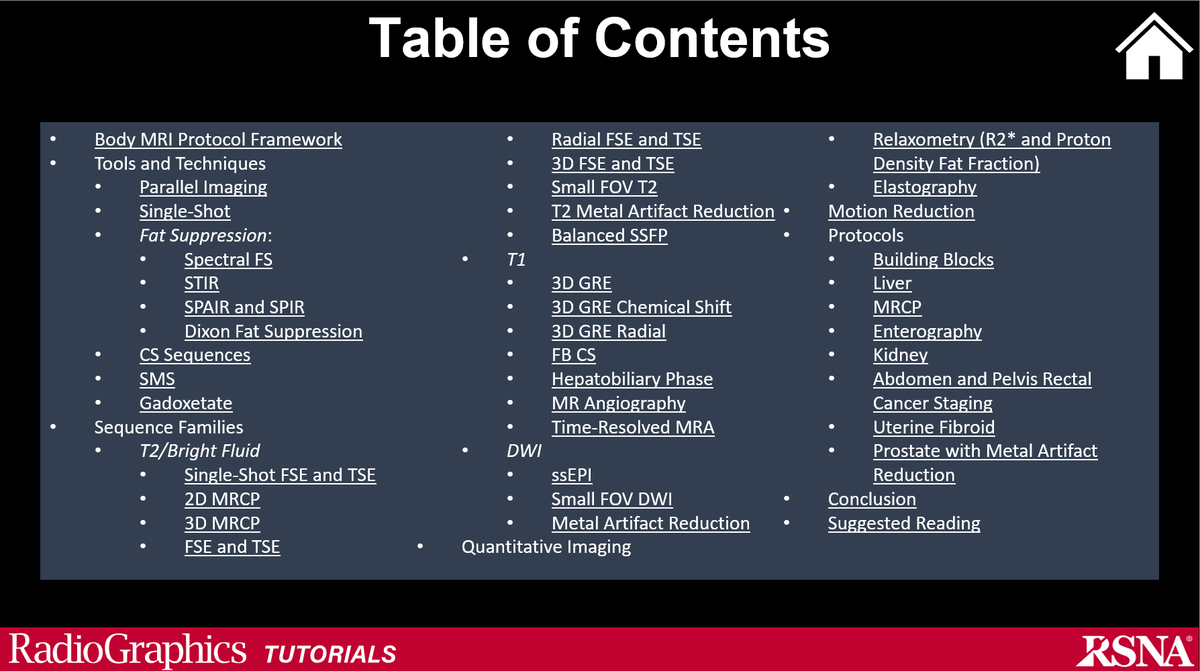

Brush up on your body MR skills with this just published review of body MRI protocols, techniques, and tips: pubs.rsna.org/eprint/KPXHYND… RadioGraphics WashUMedMIR

Looking to update your knowledge of body MRI pulse sequence physics and take a deeper dive into clinically relevant MR physics? Explore our RadioGraphics Tutorial entitled Body MRI Pulse Sequences: Atlas and User Guide at: pubs.rsna.org/doi/10.1148/rg… WashUMedMIR Test Account